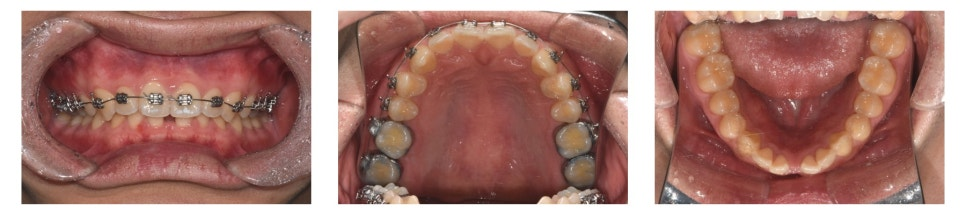

브라켓(bracket)과 밴드(band)를 부착하여 치아 배열을 진행하였습니다.

깊게 물리는 상태라 하악 치아에 장치를 바로 부착하면 상악 치아에 걸릴 수 있었습니다.

따라서 상악 먼저 장치를 부착하여 배열을 시작했습니다.

약 4개월 후 상악 배열이 어느 정도 진행되면서, 하악에도 장치를 부착할 수 있는 공간이 확보되었습니다.

이후 하악에도 장치를 부착하여 배열을 진행했습니다.